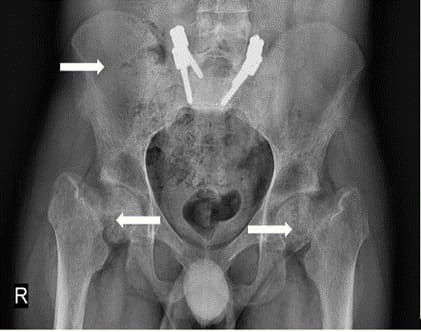

A 28-year-old otherwise healthy male, developed skeletal, muscular and joints pain 5 years’ prior to his arrival to our institution. The patient had no history of smoking, ethanol intake, antiseizure medication, antacid abuse, steroid use, bisphosphonates or antidiabetic medications. Due to severe low back pain, the patient was diagnosed with L5-S1 bilateral spondylolisthesis and treated with bilateral pedicle screw hook fixation (Figure 1). In spite of the treatment, the patient continued to deteriorate, he became bedridden due to severe pain and fatigue, until his referral to our institution. Upon his arrival, the radiological survey revealed a convex deformity of both his hips with subcapital fracture of the right femur (Figure 1), multiple rib and vertebrae fractures (Figure 2A), fracture of the left scapula (Figure 2B), fracture of the sternum (Figure 2C), severe pectus carinatum with thoracic and sacral kyphosis (Figure 2D). A DXA study showed severe osteoporosis (T score <-2.5) [10]. Biochemical investigations revealed a low serum phosphorus level (1.1 mg/dL) and an elevated alkaline phosphatase level (287 u/l). Serum creatinine, calcium, and albumin were found to be normal. Serum 1,25-dihydroxyvitamin D level was low (10.1pg/ml). This data led to the suspicion of TIO. As a result, we evaluated the levels of FGF23 in the blood. The plasma FGF23 levels were collected from the right and left median cubital veins and from the femoral veins and showed levels of 1802 pg/ml, 1816 pg/ml, 2319 pg/ml, and 1806 pg/ml, respectively (normal reference range: 23.2 – 95.4 pg/ml). A 68GA-DOTATATE PET/CT scan demonstrated uptake in a 2.5 cm x 1.6 cm lesion located in the right popliteal fossa. The patient was referred to the orthopedic oncology surgical unit with the diagnosis of a possible phosphaturic mesenchymal tumor. After clinical evaluation of the tumor, MRI and CT studies with contrast injection of the right knee were performed. The studies demonstrated a soft tissue lesion in the right popliteal fossa, 2.3 cm in diameter, located adjacent to the popliteal vessels, the tibial nerve and the common peroneal nerve (Figure 3). Once the dimensions and the borders of the lesion were defined and confirmed, surgical treatment was recommended. A wide resection of the tumor was performed. Histopathological examination disclosed a mesenchymal tumor, composed of spindle cells and osteoclast-like giant cells, with free surgical margins. 14 hours post-surgery, blood samples presented a normal FGF23 level (52.67 pg/ml). One-week post-surgery, the levels of serum phosphorus also returned to normal (Figure 4).

Figure 1: XRAY of the pelvis and hips demonstrating bilateral coxa vara with subcapital fracture of the right femur. Bilateral pedicle screw hook fixation can be observed due to the treatment of bilateral spondylolysis.